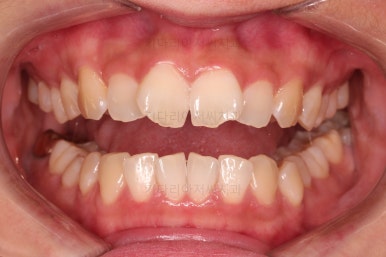

오늘 부산앞니부분교정 키다리아저씨치과에서 소개해 드릴 환자분은 위아래 앞니가 삐뚤어 부분교정으로 개선하고자 하셨던 분입니다.

1. 초진

초진 시 입안의 모습입니다.

어금니 쪽은 약간 삐뚤긴 하지만 꼭 교정해야 할 정도는 아니고, 불편감 없이 비교적 잘 맞물리는 상태였습니다.

다만, 앞니ㅉㄱ이 공간이 부족해서 중간 치아들이 많이 회전되어있는데, 이를 환자분들의 표현에 따르면 "나비치아" 라고 부릅니다.

위아래 중간 앞니가 모두 나비치아처럼 되어있고요.

윗니가 아랫니보다 앞쪽으로 나와 있는 모습에 아래앞니가 윗니쪽으로 깊숙이 올라간 "과개교합" 양상을 보였습니다.